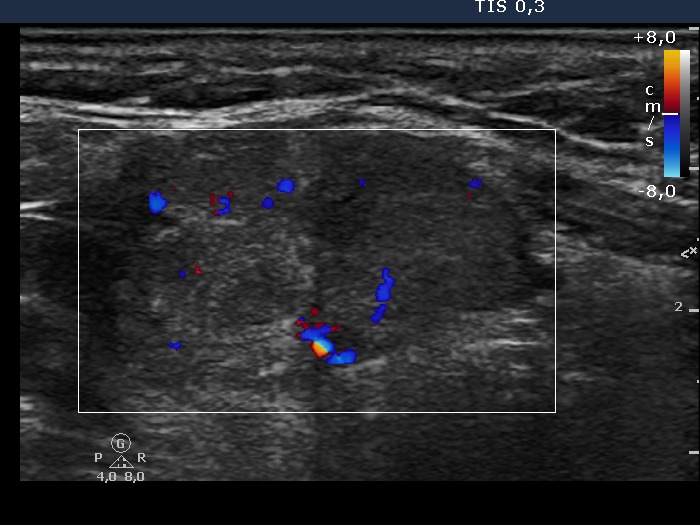

Isthmus, transverse view, color Doppler mode. The intranodular blood flow is increased.